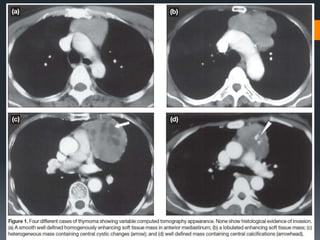

THYMOMA Thymoma is thecommonest primary tumour of the anterior mediastinum. It occurs most frequently in adults older than 40 years and is rare in children and adolescents. Thymoma appears as a well-defined, rounded or lobulated anterior-superior mediastinal mass anterior to the aortic root. The mass contains either homogenous or heterogeneous contents depending on the presence of haemorrhage, necrosis, or cyst formation. Calcific foci are seen on CT in a minority of patients